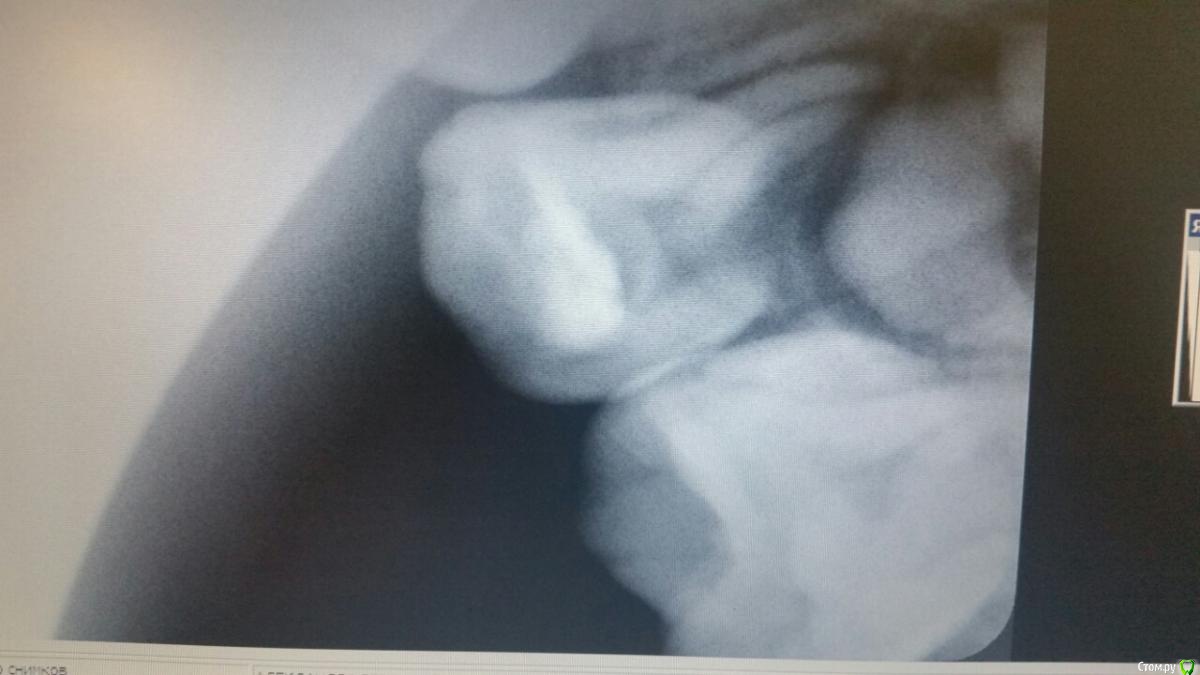

Ребенку скоро 4 года. Чуть более года назад был пролечен поверхностный кариес верхней четверки. В настоящий момент над пролеченным зубом возник небольшой белый "прыщик". Сходили к доктору, удалили старую пломбу, пульпа твердая, живая. Пульпу вскрывать не стали. Сделали снимок. Получили рекомендацию смотреть состояние в динамике. Ребенок ни на что не жалуется, зуб не шатается, при накусывании этим зубом твердых предметов боли не ощущает. Что это периодонтит? Ждать или принимать срочные меры? Спасибо!